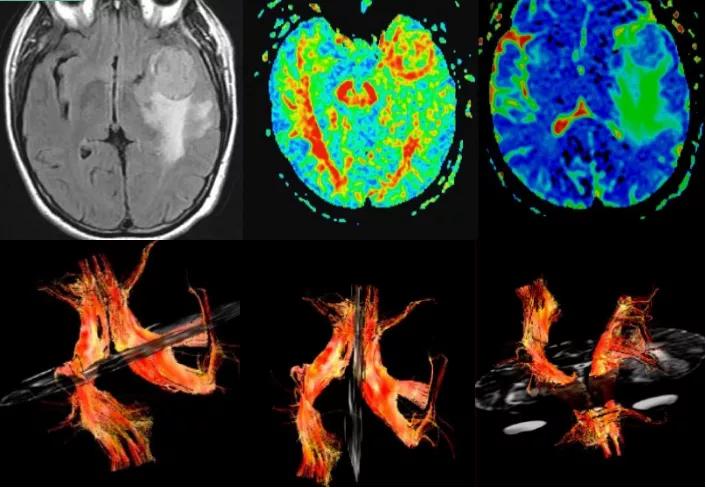

脑外伤的应用

弥漫性轴索损伤的患者中,绝大多数都会表现出弥散各向异性程度的改变。外伤后弥漫性轴索损伤最初的24小时里,在普通MR上表现正常的白质可能会出现弥散各向异性指数轻度的下降。而外伤几周后这种下降会很明显。

外伤患者DWI显示脑干损伤,DTT图示白质纤维束扭曲变形及移位

此外,对于一些脑挫裂伤的患者,DTI也可显示挫伤区与纤维束的关系,同样有助于判断白质纤维束损害程度与身体相应部位的功能障碍的关系,有助于判断临床治疗效果、判断病人恢复、预后。

脊髓损伤患者,显示纤维束明显扭曲、变形、部分断裂